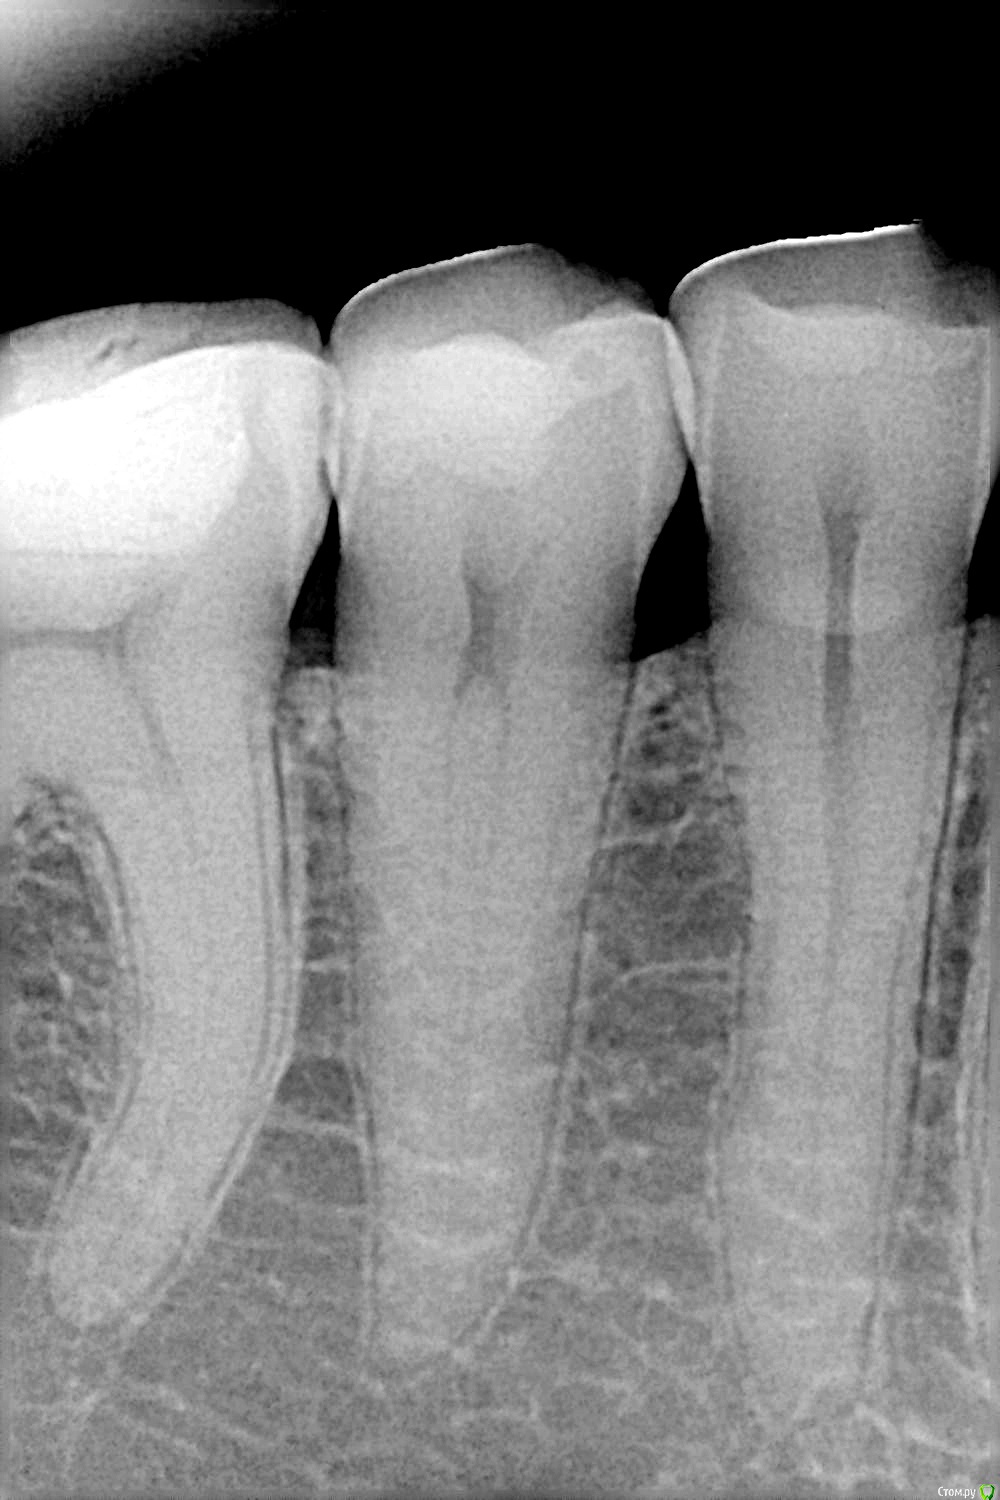

imageaz Опубликовано 3 сентября, 2015 Поделиться Опубликовано 3 сентября, 2015 Здравствуйте, товарищи стоматологи! В период с 5 по 11 августа были пролечены три зуба, 7, 5, 4, ...7,5-средний кариес, 4-запечатали фиссуры... Протокол соблюден...Сначала была гиперчувствительность, и ныли, списали на постпломбировочные боли(в течении недели) Пошла третья неделя, зубы ноют,( по ощущения вроде 7 или 5) на ночь пью найз половину таблетки, хватает на сутки... Начало ныть ухо, и ощущения в виске, по снимку все вроде нормально, есть небольшое воспаление на корне семерки, вскрыли пломбу, поставили лечебный цемент, прошло четыре дня, боли продолжаются...Ни я, ни стоматолог не можем понять, какой конкретно зуб болит(дули, стучали, прикладывали холод)... Вскрывать все пломбы, и депульпировать??? Снимки прилагаю, может, кто-нибудь увидит, что мой стоматолог не видит...Заранее спасибо! 1 Ссылка на комментарий

Stomart Опубликовано 3 сентября, 2015 Поделиться Опубликовано 3 сентября, 2015 Попросите доктора обратить внимание на 6й зуб, там пломба располагается близко к нерву. 1 Ссылка на комментарий